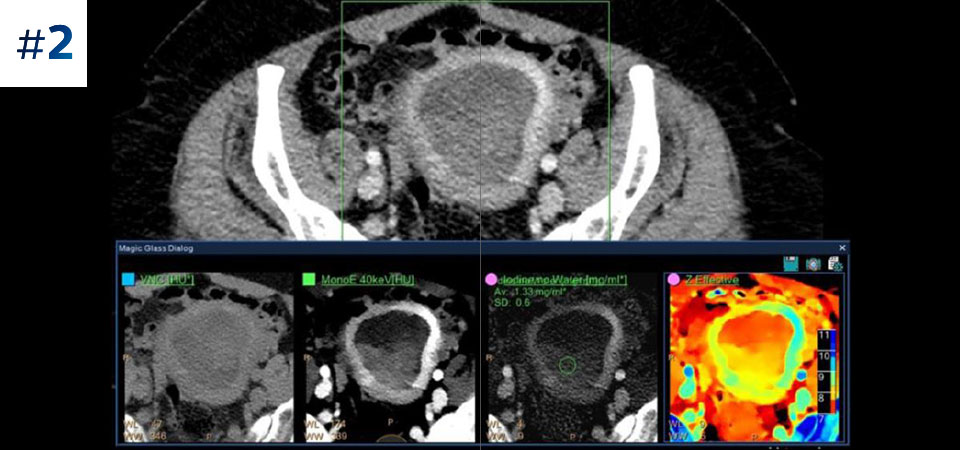

Observe las diferencias entre un detector espectral CT y un CT Convencional

Aprenda sobre las ventajas del detector espectral CT